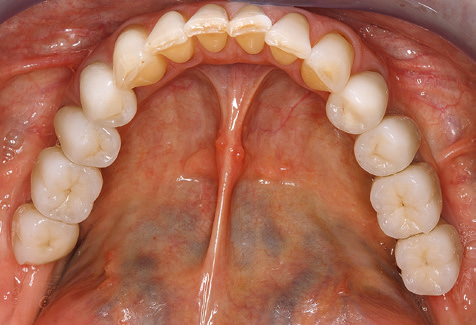

Summary

Standardised and regular risk-adapted care in the scope of SPT is the key to treatment success for the clinical long-term success in periodontically compromised patients. This is particularly true for patients fitted with implants following successfully completed periodontal treatment (Fig. 11a and b).

Fig. 9: The accessible implant and tooth surfaces are polished with polishing cups and suitable polishing compounds. – Fig. 10: Repeat instruction in the use of appropriate aids for oral hygiene at home should also form part of SPT. – Fig. 11a and b: Clinical situation 12 years after insertion of the prosthetic restoration. During this period, only a veneering ceramic fracture on tooth 47 and the requirement for endodontic treatment of tooth 12 were observed. All restorations are still functioning as intended.